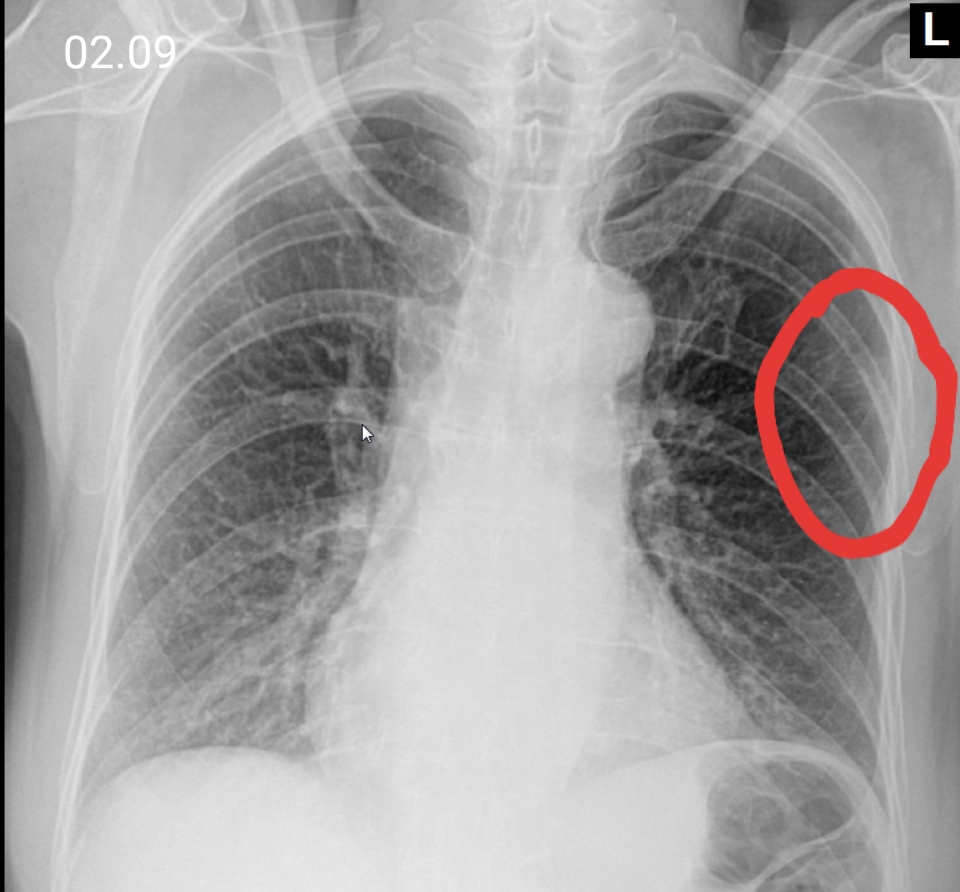

Симптомы и признаки туберкулеза: как распознать заболевание

Раздел: Визуальные уроки